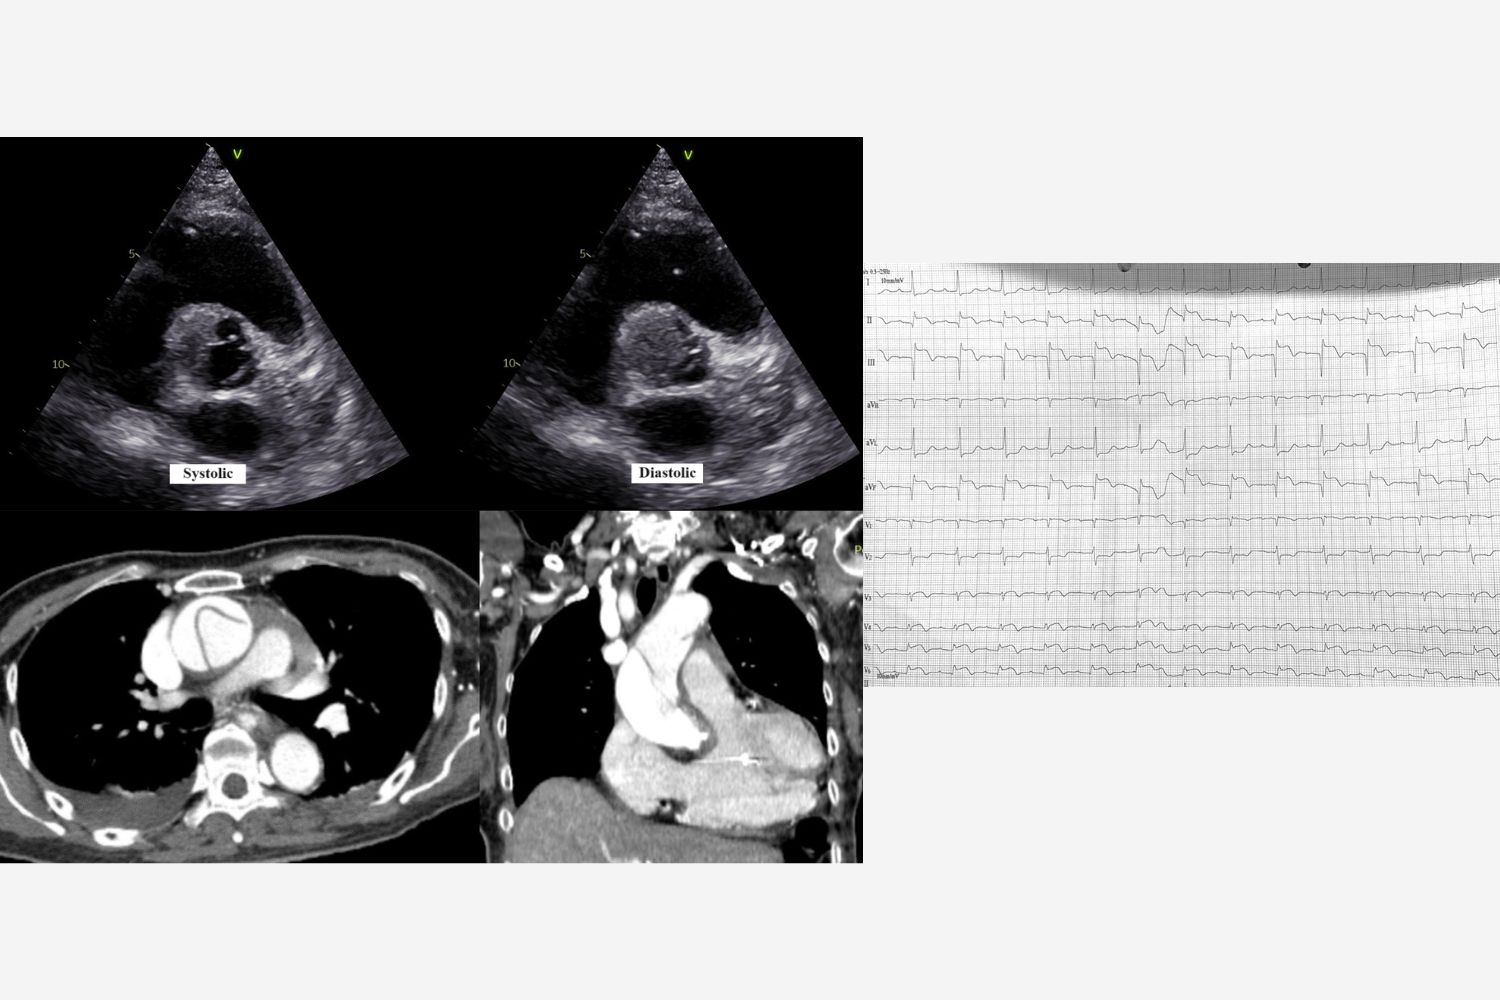

Image of the Week - 15 May 2024

Doctor Nik Ahmad Hilmi Nik Mohd Zaid

Doctor Mohd Khairi Othman